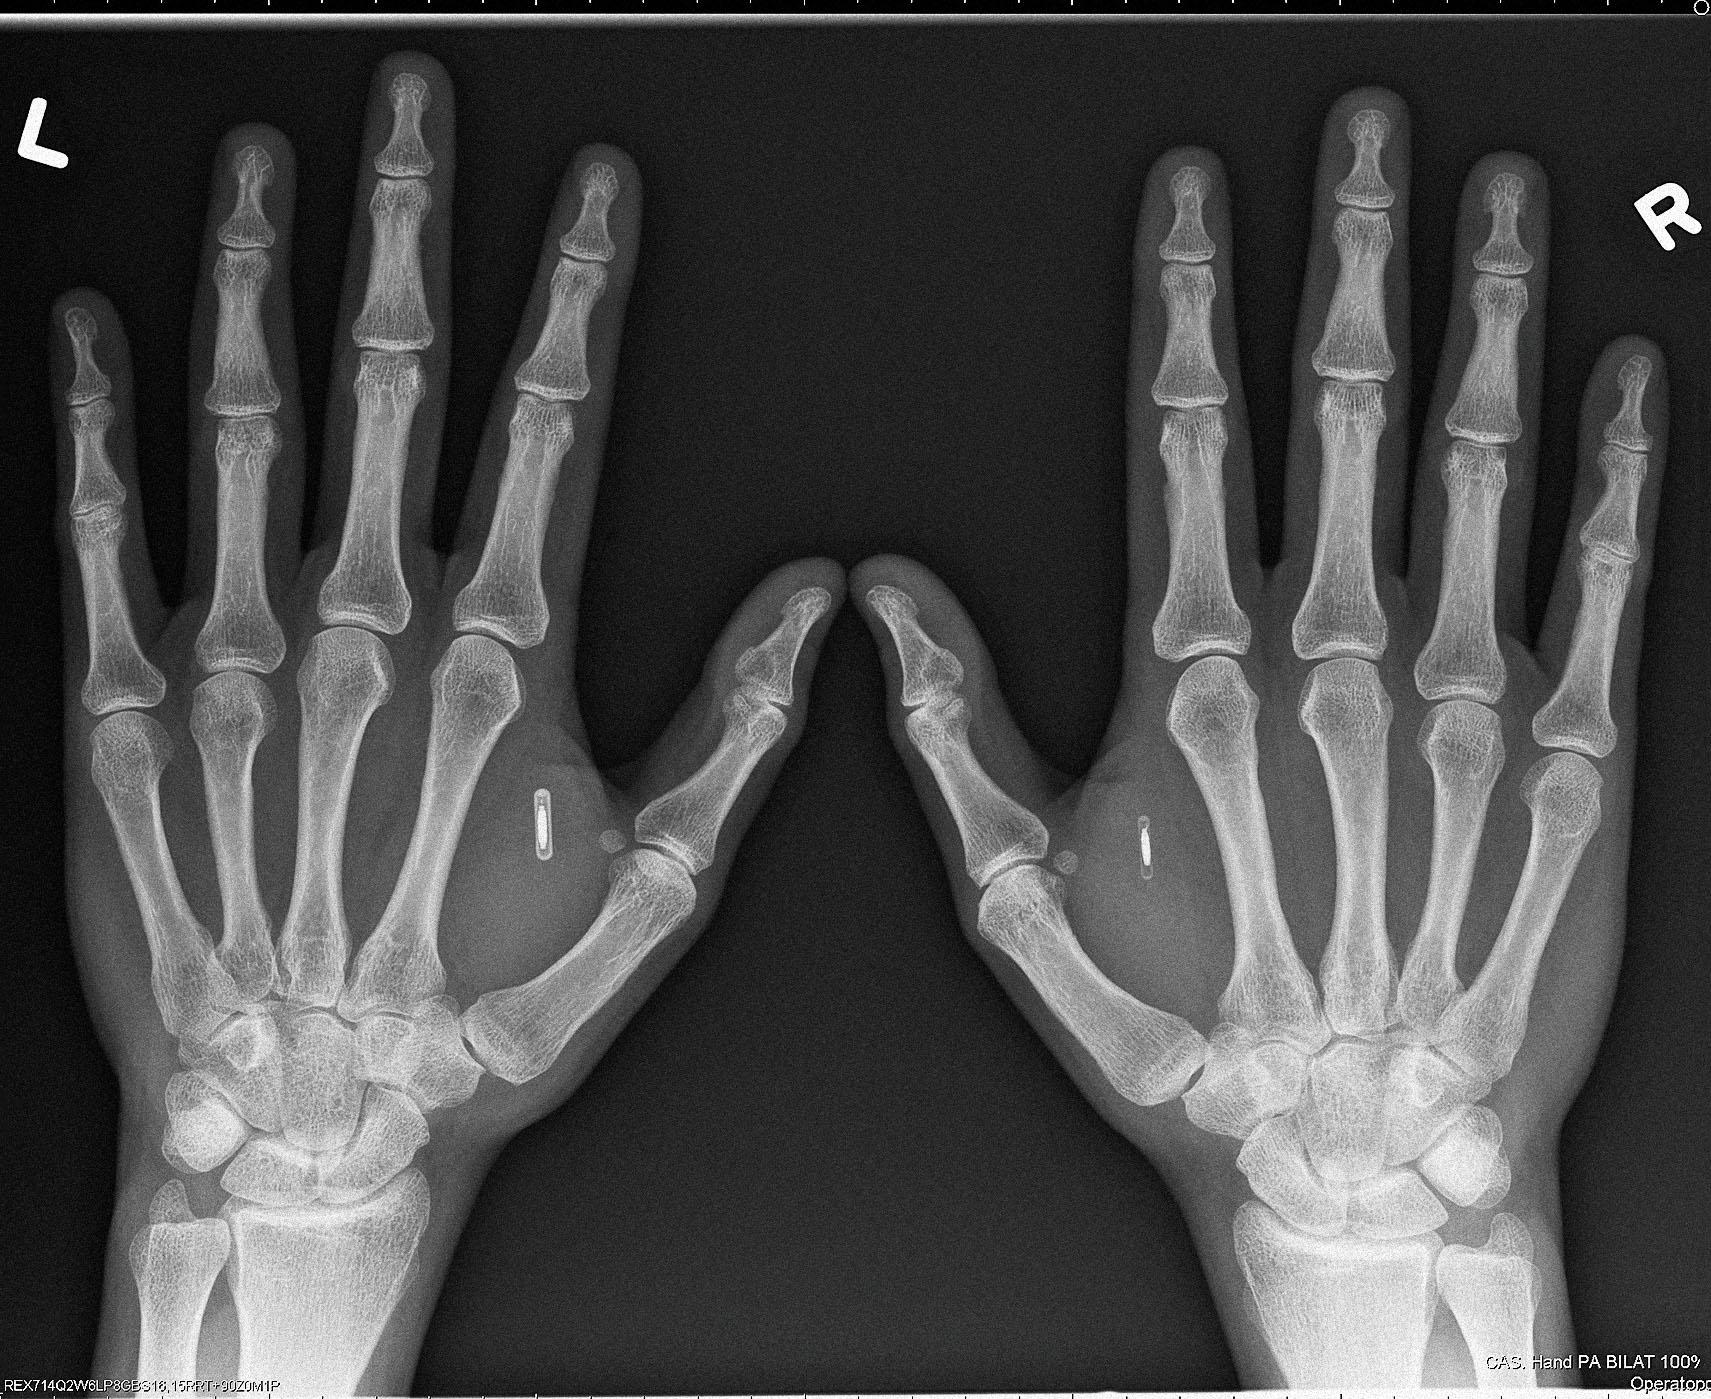

Цена на чипы разнится в зависимости от серии. Серия X — самые популярные из-за простоты установки NFC- и RFID-транспондеры. Их Dangerous Things продает по $79, они не требуют подзарядки и способны нести информацию о пользователе, его электронные ключи. Следующая серия — Flex. Это чип в гибком биополимере стоимостью $200. Если девайсы серии X можно вживить только под кожу между большим и указательным пальцем «ветеринарной» иглой с чуть увеличенным диаметром, то Flex размещаются чуть выше запястья, а их «установка» требует небольшой хирургической операции.